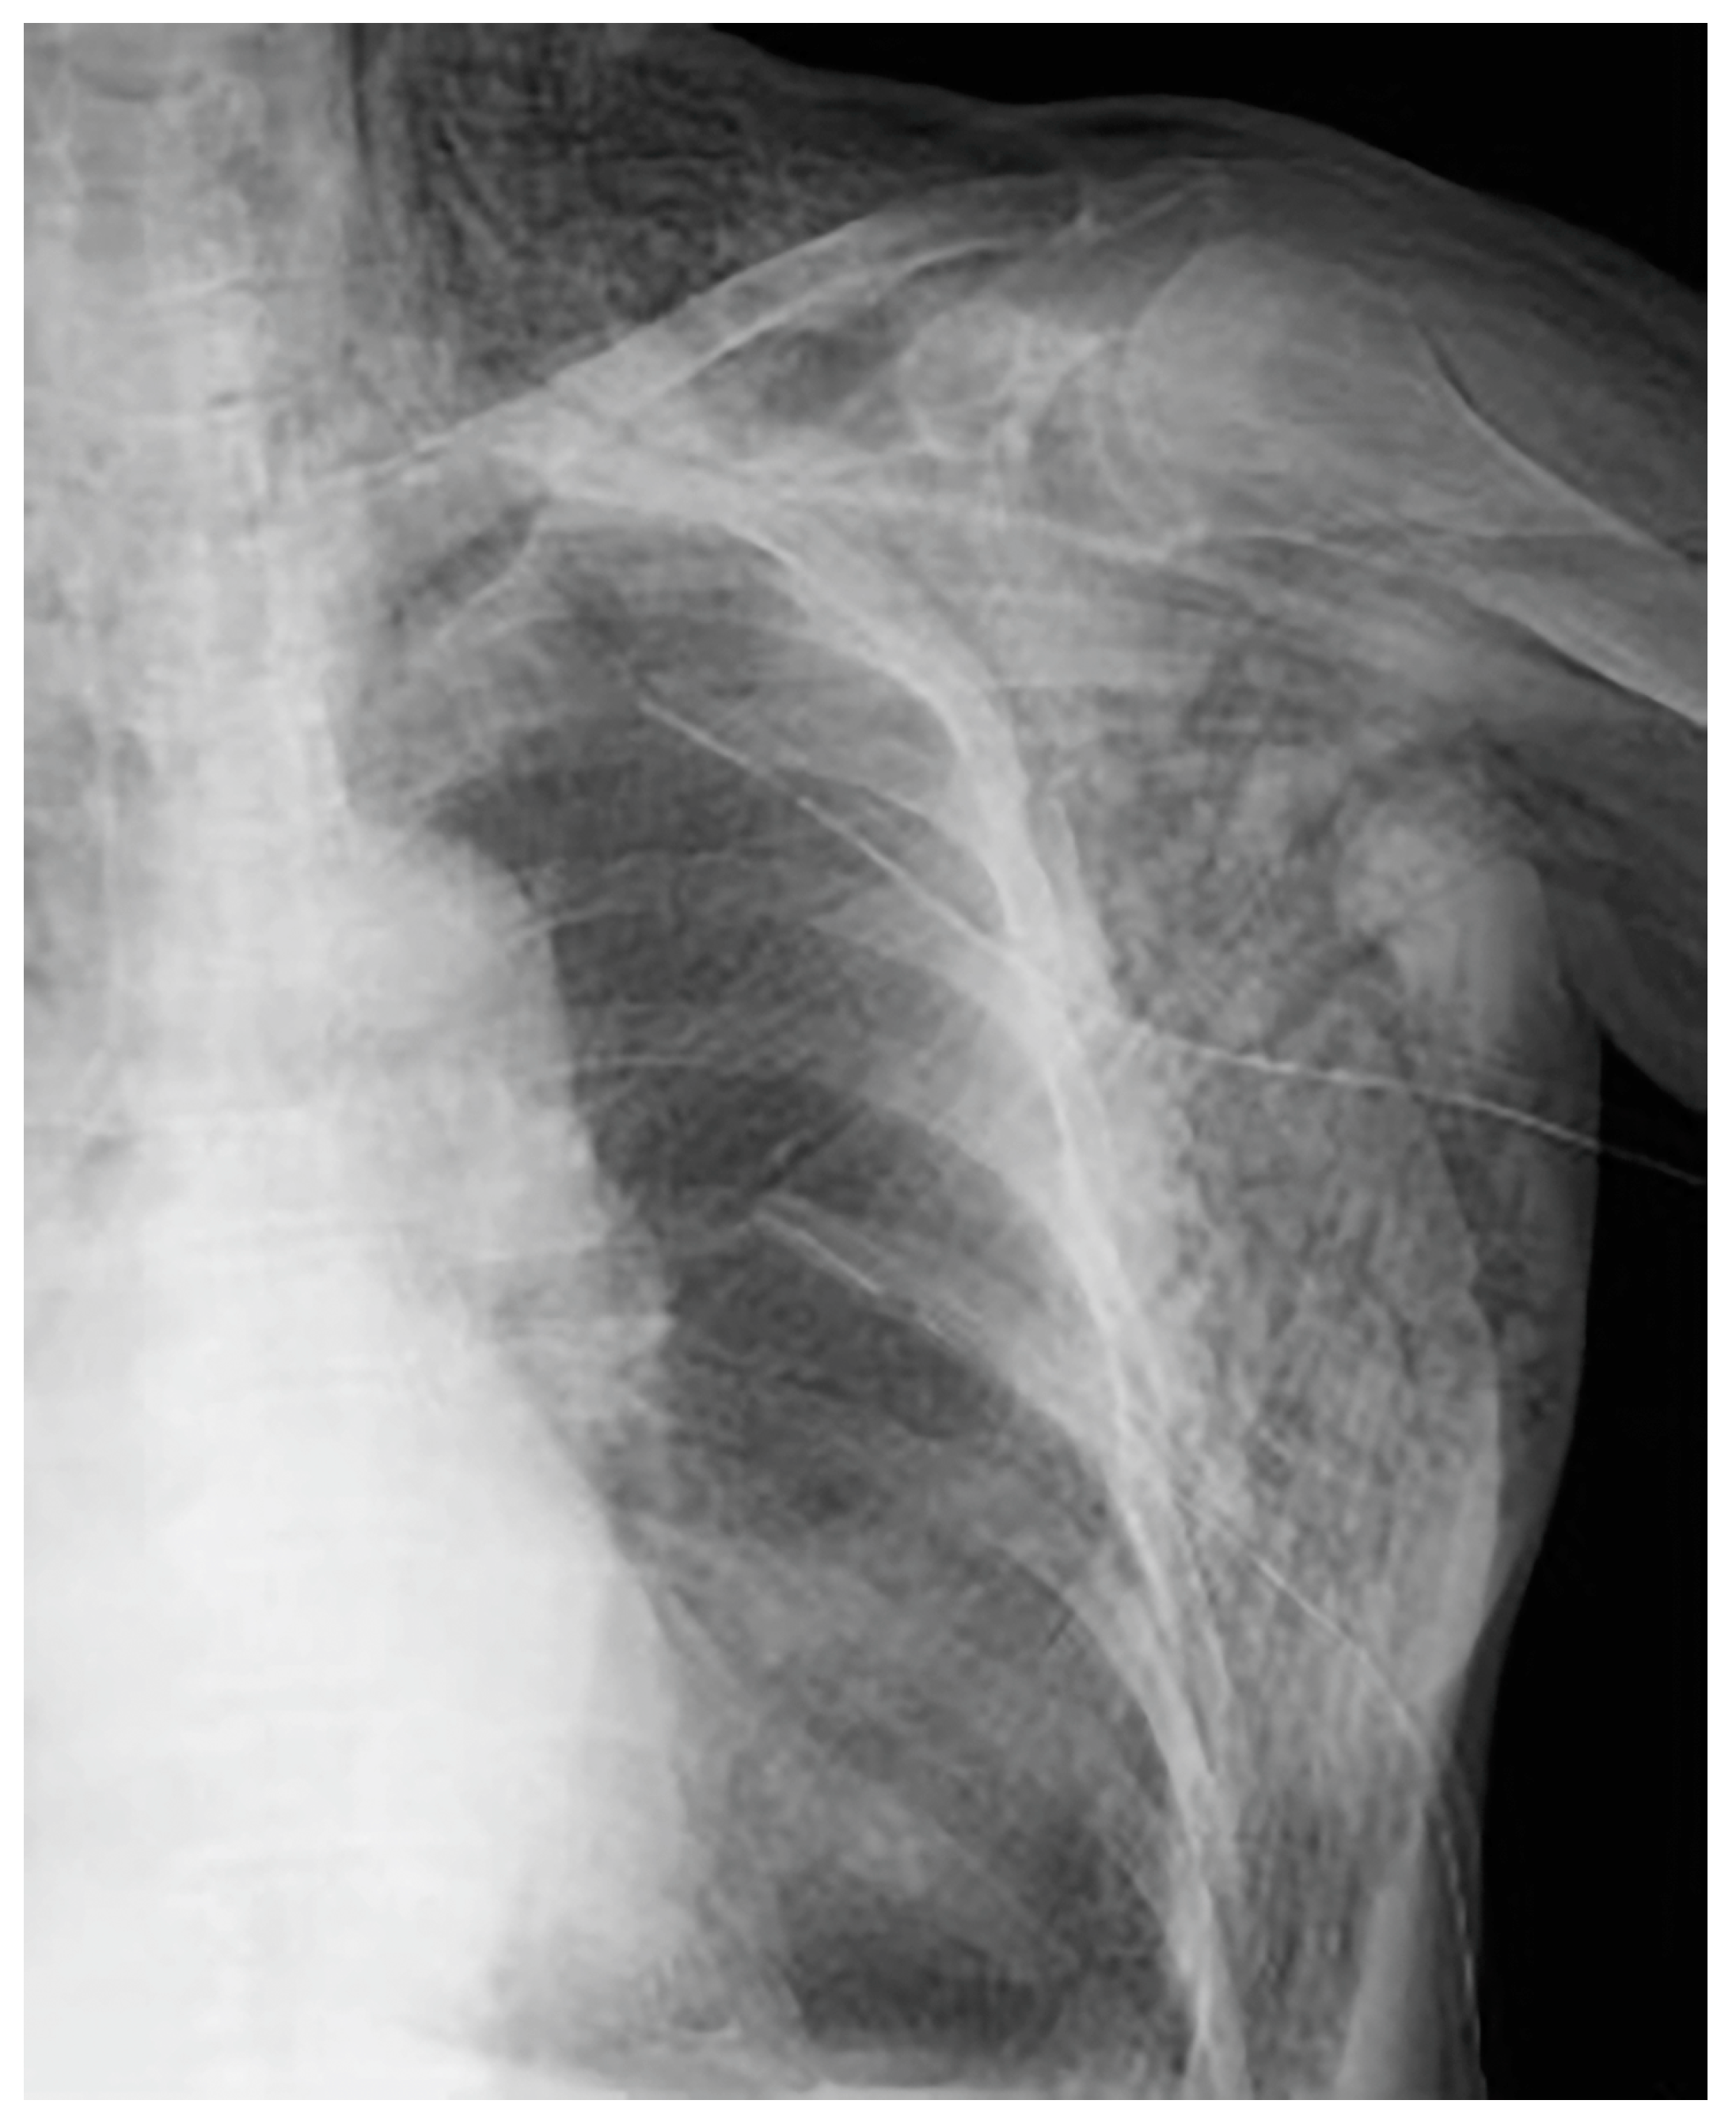

We were able to confirm that the thoracic drain position was not a problem, and neither mediastinal nor subcutaneous emphysema worsened thereafter (Figure 5a,b).

Figure 5.

The clinical course after placement of the first thoracic cavity drain. Day 1 (a), Day 4 (b).

No air leaks were observed; however, respiratory fluctuations were observed. Day by day, the subcutaneous emphysema showed a tendency to improve. One drain was removed on day 9 following drain insertion and the other drain on day 13. No worsening of subcutaneous emphysema was observed after drain removal. The patient was discharged on day 4 after drain removal (Figure 6).

Figure 6.

The day before hospital discharge. Mediastinal and subcutaneous emphysema had improved.